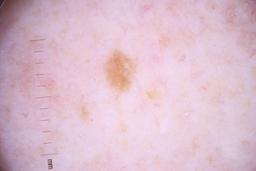

ISIC_4077341

Public

Information

- Created

- Dimensions

- 5184 x 3456

- Attribute to

- The University of Queensland Diamantina Institute, The University of Queensland, Dermatology Research Centre

- License

- CC-BY

- Used in

- Challenge 2020: Training

- Belongs to

- IP_1969685 IL_9238622

Clinical

| Field | Value |

|---|---|

| acquisition_day | 1 |

| age_approx | 50 |

| anatom_site_1 | Trunk |

| anatom_site_2 | Anterior trunk |

| concomitant_biopsy | False |

| dermoscopic_type | contact non-polarized |

| diagnosis_1 | Benign |

| diagnosis_confirm_type | serial imaging showing no change |

| family_hx_mm | False |

| image_type | dermoscopic |

| lesion_id | IL_9238622 |

| patient_id | IP_1969685 |

| personal_hx_mm | True |

| sex | male |

Columns

Showing first 50 images.